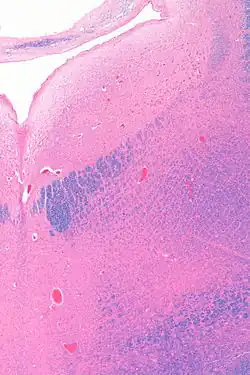

The locus coeruleus (LC) is located in the posterior area of the rostral pons in the lateral floor of the fourth ventricle. It is composed of mostly medium-size neurons. Melanin granules inside the neurons contribute to its blue colour. Thus, it is also known as the blue nucleus, or the nucleus pigmentosus pontis (heavily pigmented pontine nucleus).[5] The neuromelanin is formed by the polymerization of norepinephrine and is analogous to the black dopamine-based neuromelanin in the substantia nigra.